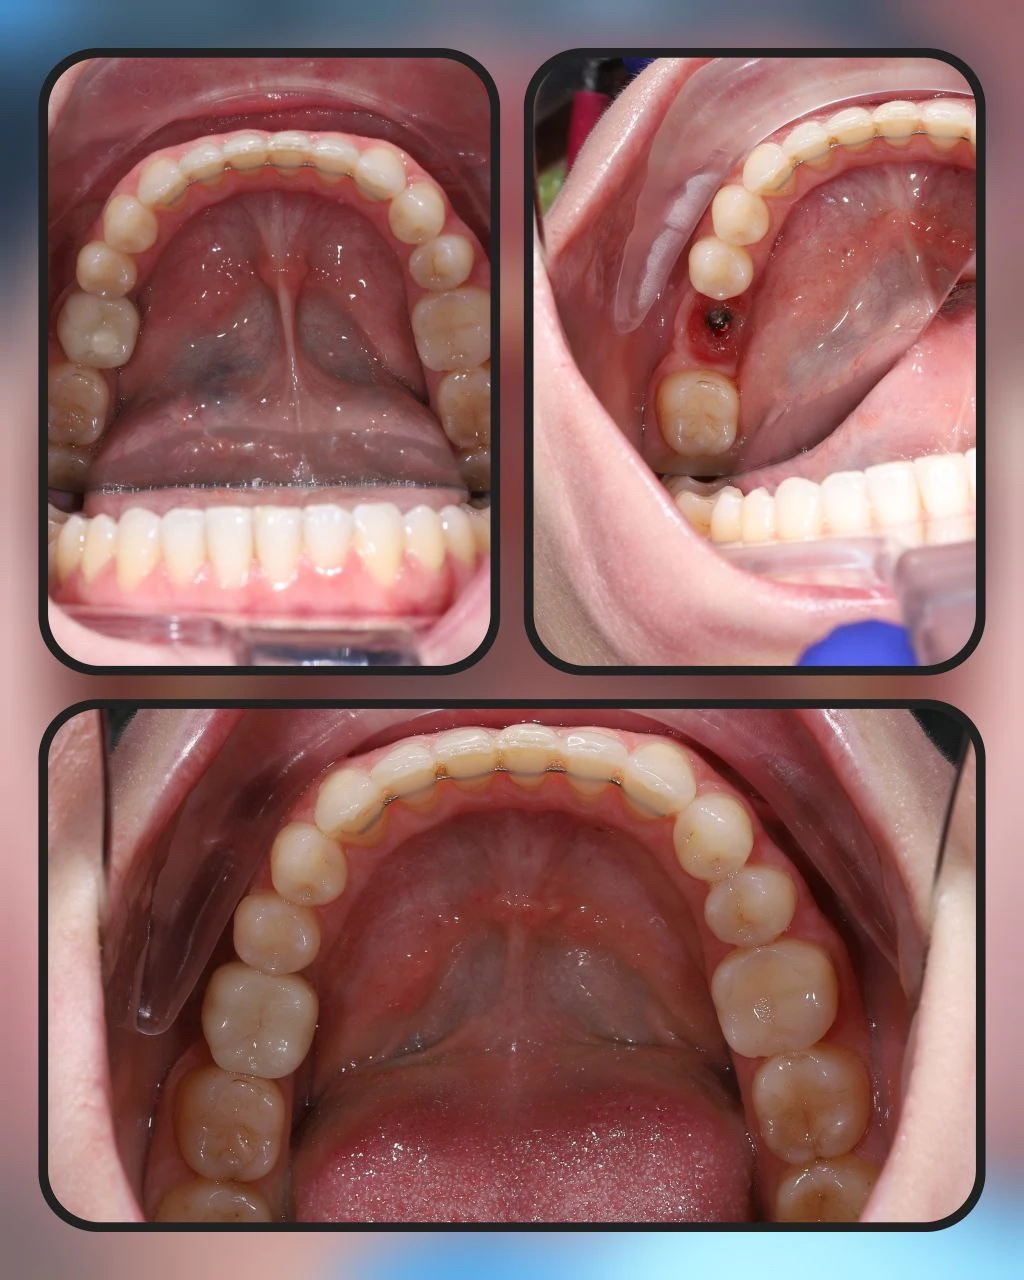

ЦК на 14.15.16.23.27 ЦК на премілах 24-26